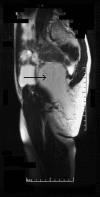

Case presentation: A 36 year old woman presented with an expanding, yet reducible, right gluteal mass, indicative of a sciatic hernia. However, magnetic resonance imaging demonstrated a large intra- and extra-pelvic fatty mass traversing the greater sciatic foramen. The tumour was surgically removed through an abdomino-perineal approach. Subsequent pathological examination revealed an atypical lipomatous tumour (synonym: lipoma-like well-differentiated liposarcoma). The patient remains free from recurrence two years following her surgery.

Conclusion: The presence of a gluteal mass should always suggest the possibility of a sciatic hernia. However, in this case, the hernia consisted of an atypical lipoma spanning the greater sciatic foramen. Although lipoma-like well-differentiated liposarcomas have only a low potential for recurrence, the variable nature of fatty tumours demands that patients require regular clinical and radiological review.